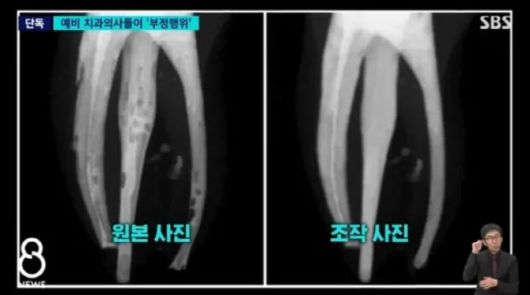

원본 엑스레이에는 신경치료 실습 과정에 나선 학생들이 제대로 치료하지 못 해 여러 군데가 구멍이 난 듯 보인다. 또 신경치료 과정에서 충전재를 꼼꼼하게 채워 넣지 않아 기포도 들어 찼다.

제대로 치료가 안 된 원본사진(왼쪽)과 포토샵으로 조작해 교수에 제출한 사진이다. (사진=SBS 캡처) |

그러나 학생들이 교수진에 제출한 사진은 이와 매우 달랐다. 기포 하나 없이 매우 깨끗하게 치료된 상태다. 일부 학생들이 포토샵 프로그램을 이용해 치료가 잘 끝난 것처럼 사진을 조작한 것이다.